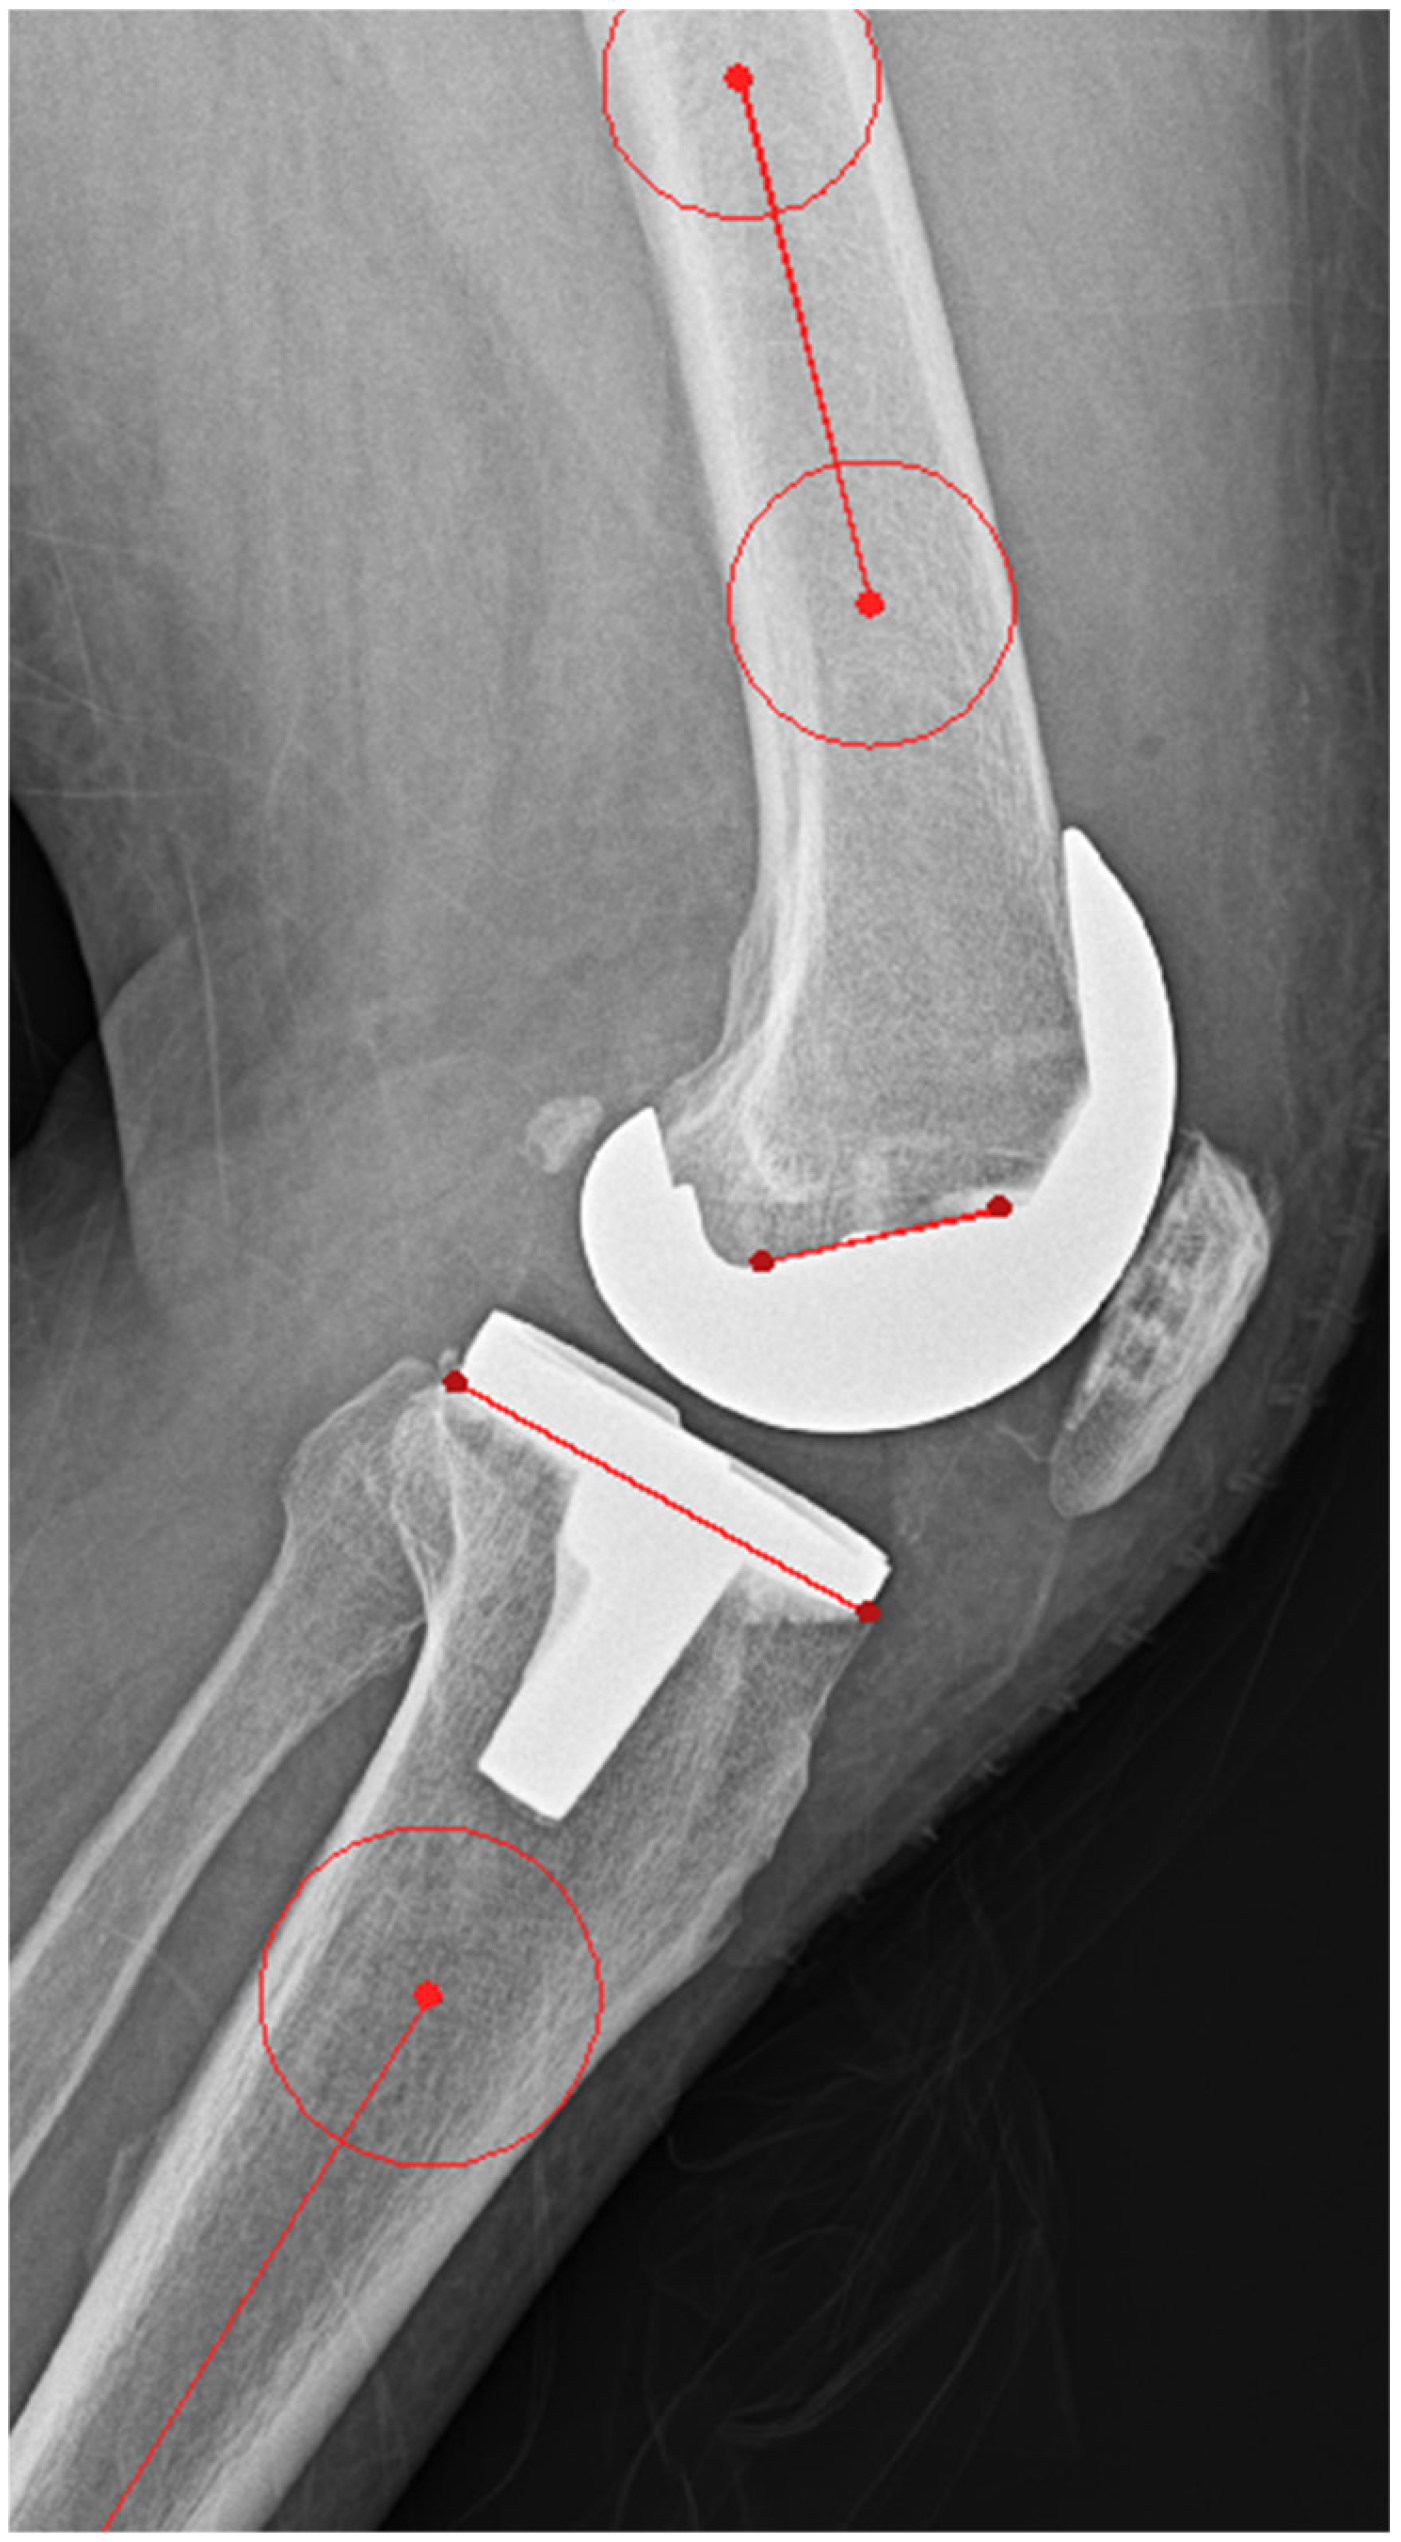

2.2. Pre-Planning and PSI Design Methods

2.3. Outcome Measurements